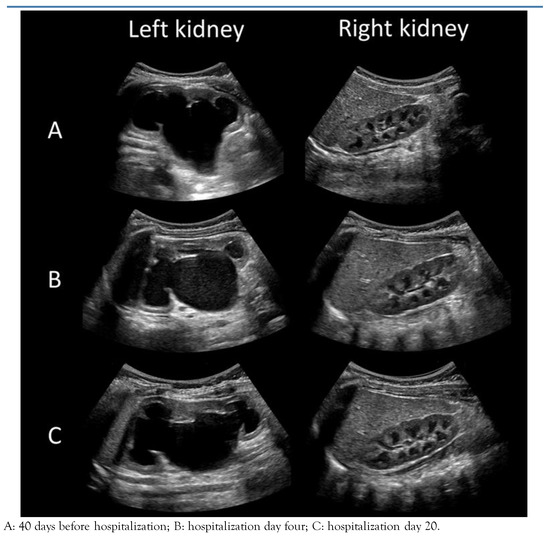

Introduction: Hypertension is occasionally associated with congenital hydronephrosis. Case report: The authors report a four-month-old boy with severe left congenital hydronephrosis and transient hypertension triggered by his first urinary tract infe...